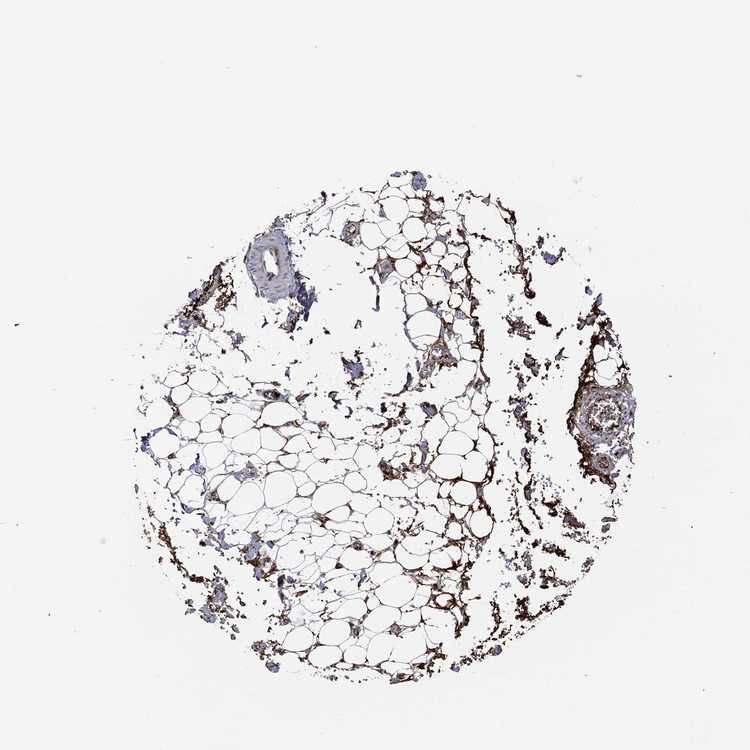

ADIPOSE TISSUE - Antibody stainingi

Antibody staining in the annotated cell types in the current human tissue is reported as not detected, low, medium, or high, based on conventional immunohistochemistry profiling in selected tissues. This score is based on the combination of the staining intensity and fraction of stained cells.

Each image is clickable and will lead to virtual microscopy that enables deeper exploration of all samples and also displays staining intensity scores, fraction scores and subcellular localization as well as patient and tissue information for each sample.

Antibody HPA027529Antibody HPA074638Antibody CAB033120

Adipocytes Not detectedMediumLow